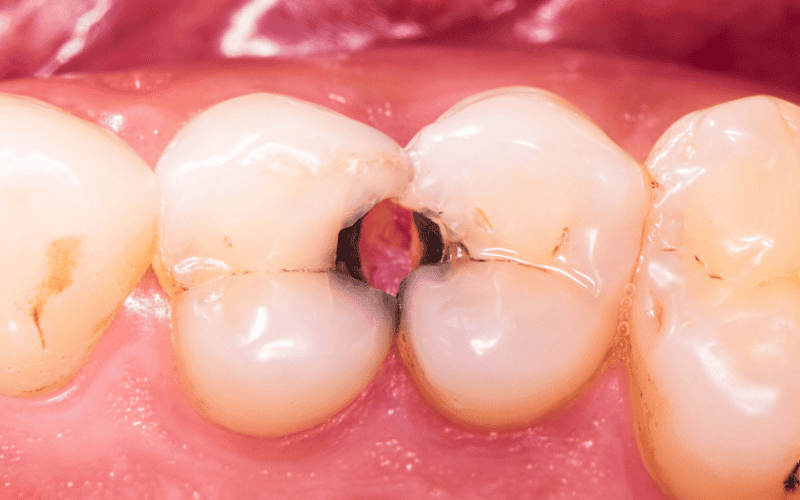

Las caries se producen cuando las bacterias presentes en la boca descomponen los azúcares de los alimentos y generan ácidos que dañan el esmalte dental. Si el daño progresa y alcanza la pulpa del diente, donde se encuentran los nervios y vasos sanguíneos, puede originarse una infección conocida como absceso dental. En este punto, el problema deja de ser local y puede extenderse a otras zonas del cuerpo.

Una infección dental no tratada puede propagarse a los tejidos cercanos del rostro y el cuello, provocando celulitis facial o infecciones profundas como la angina de Ludwig, una condición grave que puede obstruir las vías respiratorias. Además, las bacterias pueden ingresar al torrente sanguíneo y causar sepsis, una respuesta inflamatoria generalizada que pone en peligro órganos vitales y puede resultar mortal si no se atiende con urgencia.